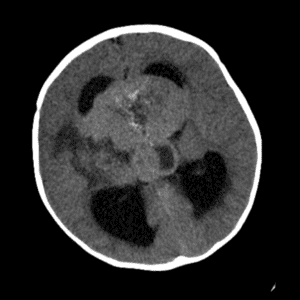

Case #41

Atypical teratoid/rhabdoid tumor (AT/RT)